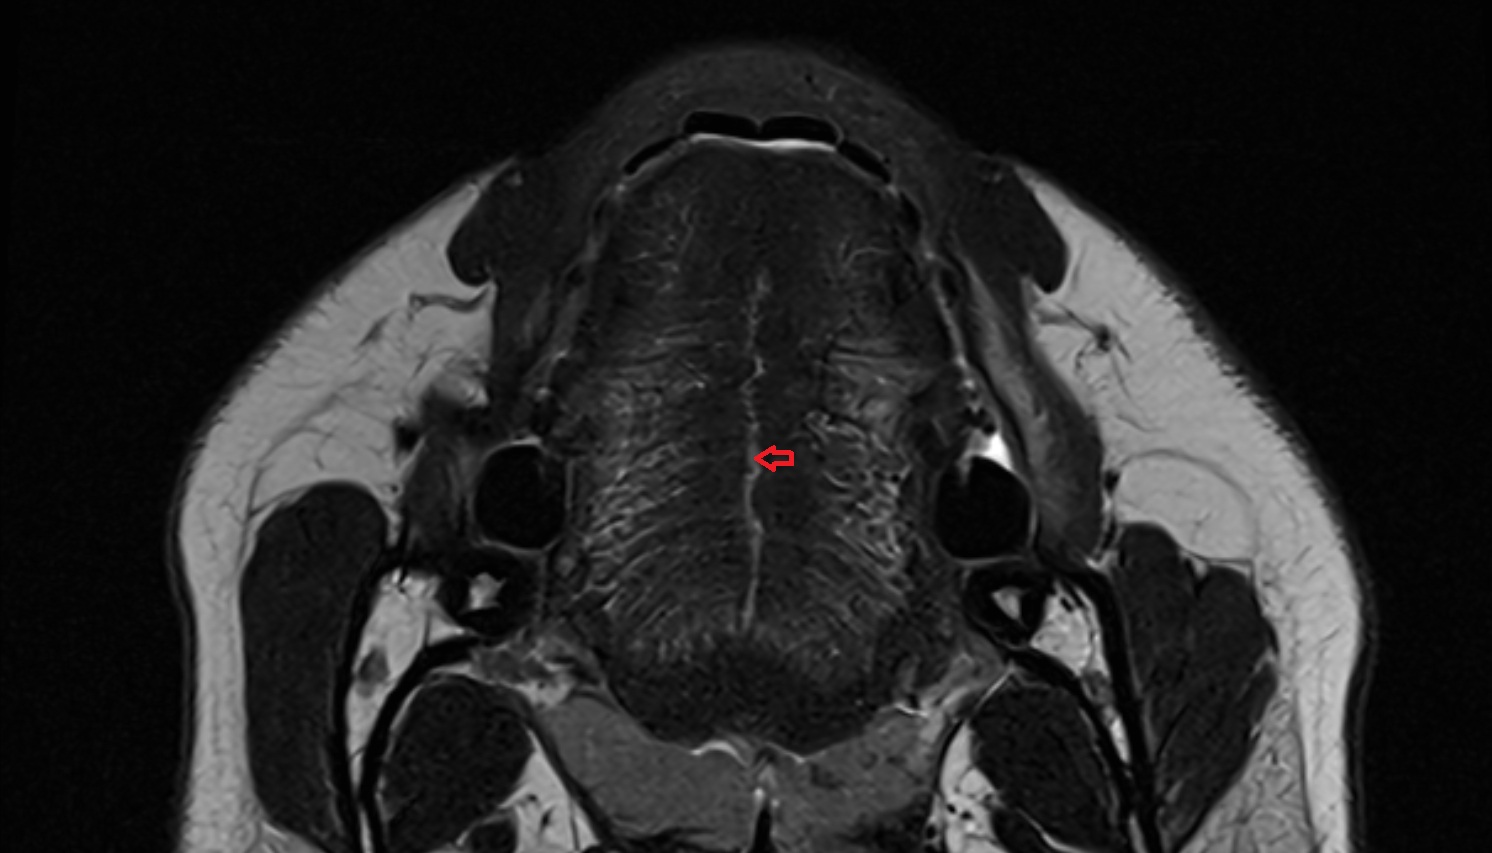

- Putamen

- Globus pallidus internal segment

- Globus pallidus external segment

- Head of caudate nucleus

- Body of caudate nucleus